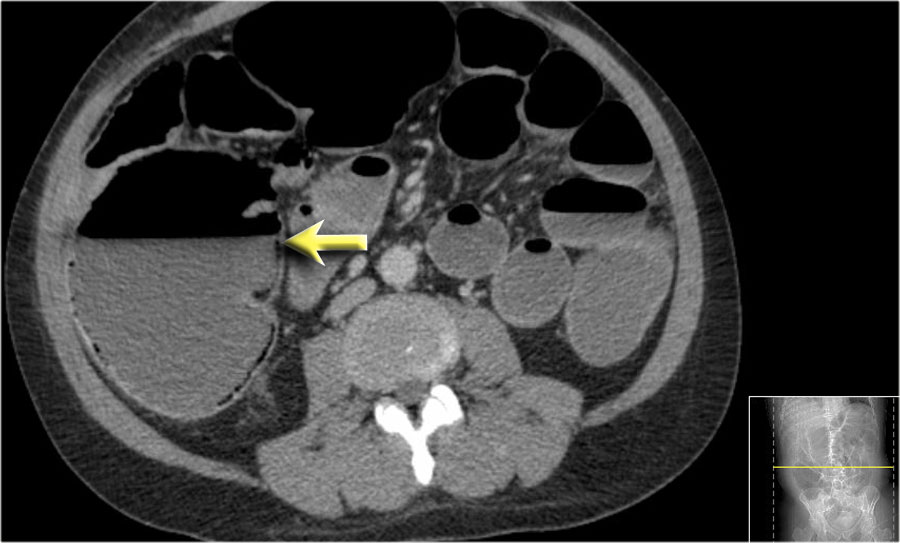

Thiếu máu cục bộ mạc treo ruột

Thiếu máu cục bộ ruột thường ảnh hưởng đến đại tràng và hay gặp nhất ở góc lách, đại tràng xuống và đại tràng sigma.

Nguyên nhân chủ yếu là do tình trạng giảm lưu lượng máu như sốc giảm thể tích hoặc suy tim sung huyết.

Đặc biệt ở người cao tuổi có dày thành ruột, cần luôn đưa thiếu máu cục bộ vào danh sách chẩn đoán phân biệt.

Một nguyên nhân đặc biệt gây thiếu máu cục bộ ruột non là tắc ruột quai kín, sẽ được thảo luận ngay sau đây.

Đây là hình ảnh bệnh nhân thiếu máu cục bộ ruột do huyết khối tĩnh mạch mạc treo tràng trên – SMV (mũi tên đỏ).

Lưu ý tình trạng ứ máu tĩnh mạch trong mạc treo ruột (mũi tên vàng).